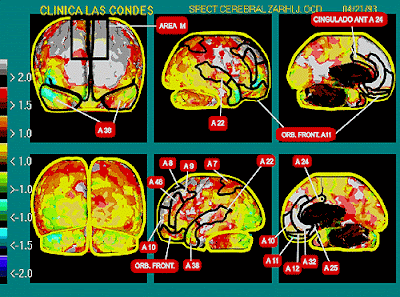

dijo: Las compulsiones son comportamientos de carácter repetitivos, que el sujeto se ve obligado a realizar a en respuesta a una idea obsesiva El trastorno obsesivo compulsivo (TOC) estuvo considerado hasta hace algunos años como una enfermedad psiquiátrica rara que no responde al tratamiento. Actualmente es reconocido como un problema común que afecta al 2 por ciento de la población. El TOC es un trastorno perteneciente al grupo de los trastornos de ansiedad caracterizado por por la complementariedad de obsesiones y compulsiones. Las obsesiones son pensamientos, impulsos, o imágenes recurrentes y persistentes que se experimentan en algún momento; causan ansiedad y malestar significativo para el sujeto que lo padece. Las compulsiones son comportamientos de carácter repetitivos, que el sujeto se ve obligado a realizar a en respuesta a una idea obsesiva. El objetivo de estos comportamientos es la prevención del malestar o la prevención de alguna situación considerada como negativa por el sujeto. No obstante estos comportamiento no necesariamente condicen que la situación a prevenir o son claramente excesivos. Las compulsiones más comunes son: lavado de manos, puesto en orden de objetos, verificar el cerrado de puertas, llaves de gas, saltas baldosas, acumular objetos, tocar ect. Dentro de los actos mentales Obsesivos encontramos, rezar, contar, repetir palabras en silencio, temor a contaminarse, temor a causar daño a otros, temor a que les suceda algo a los padres o familiares, necesidad de confesar. Podríamos hacer una vasta clasificación según las conductas que prevalece a la hora de presentar un Trastorno Obsesivo Compulsivo. dijo: · Lavadores y limpiadores: son personas a las que carcomen obsesiones relacionadas con la contaminación a través de determinados objetos o situaciones. · Verificadores: las que inspeccionan de manera excesiva con el propósito de evitar que ocurra una determinada catástrofe. · Repetidores: son aquellos individuos que se empeñan en las ejecuciones de acciones repetitivas. · Ordenadores: son personas que exigen que las cosas que les rodean estén dispuestas de acuerdo con determinadas pautas rígidas, incluyendo distribuciones simétricas. · Acumuladores: coleccionan objetos insignificantes, de los que no pueden desprenderse. · Ritualizadores mentales: acostumbran a apelar a pensamientos o imágenes repetitivas con el objeto de contrarrestar su ansiedad provocadora de ideas o imágenes, que constituyen las obsesiones. · Atormentados y obsesivos puros: experimentan pensamientos negativos reiterados, que resultan incontrolables y bastante perturbadores. · Sexuales: consiste en pensamientos sexuales recurrentes, que incluyen sobre todo un temor exagerado a ser homosexual Todas las personas presentamos en algún momento de nuestra vida un comportamiento de índole obsesiva o compulsiva, pero los mismos suelen ser insignificantes para la persona y no les interfiere en su vida. Se convierten en un malestar clínico significativo: Cuando las obsesiones o compulsiones representan pérdida de tiempo, esto supone más de una hora al día. Cuando interfieren marcadamente en la rutina diaria de la persona, en su relaciones laborales o académicas, en su vida intima o social. Cuando la persona reconoce que sus rituales están siendo excesivos, pero no los puede evitar, porque la realización del mismo le da la “tranquilidad” de que no le va a suceder un mal peor. Es verdaderamente un desgaste psíquico y físico importante el que invierte una persona que presenta los síntomas de un T.O.C ya que destina parte representativa de su tiempo organizando esquemas de protección excesivos, sobre determinada situaciones que son cotidianas. Desde luego que la obsesión y o las compulsiones tiene su origen en algún pensamiento de índole negativa donde el sujeto se ve amenazado por determinada circunstancia situación que genera un grado de tensión constante en la persona. Las personas que se sienten identificadas con alguno de estos síntomas, no deben dejar pasar más tiempo en realizar una consulta, porque minuto tras minuto se va perdiendo calidad de vida. Fuente